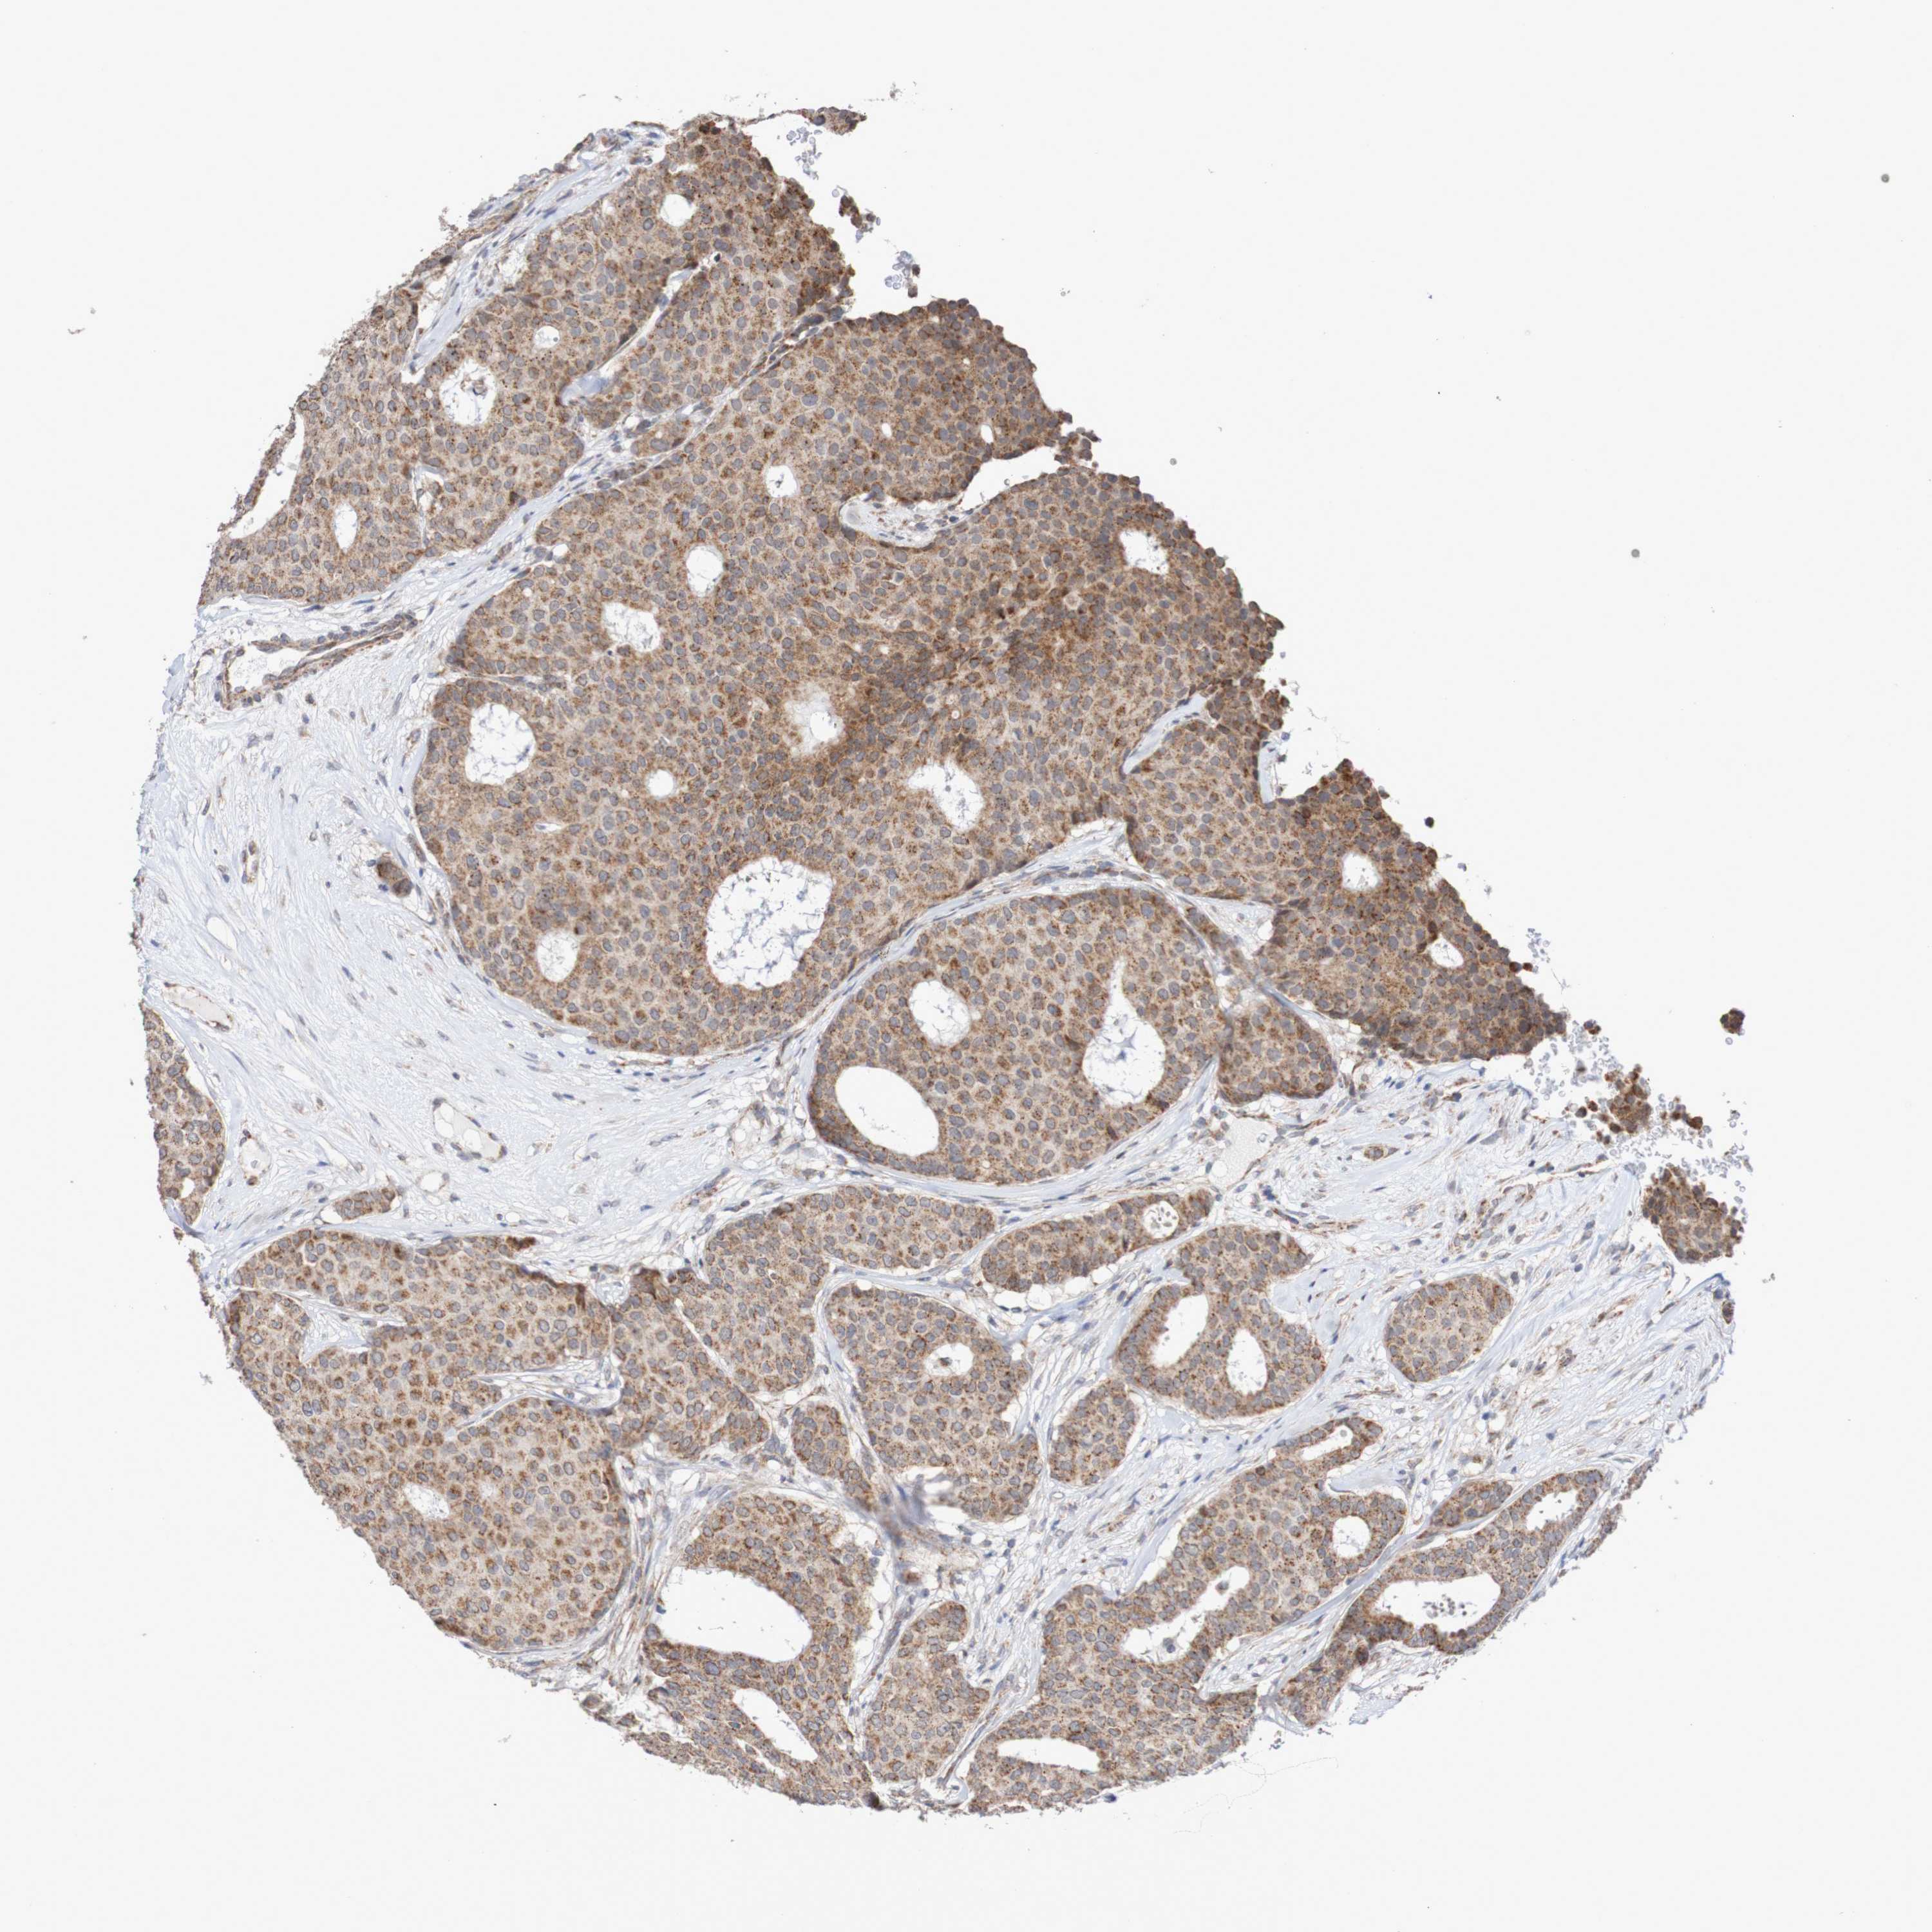

CANCER BREAST CANCER Show tissue menu

Breast cancer

Human cancer